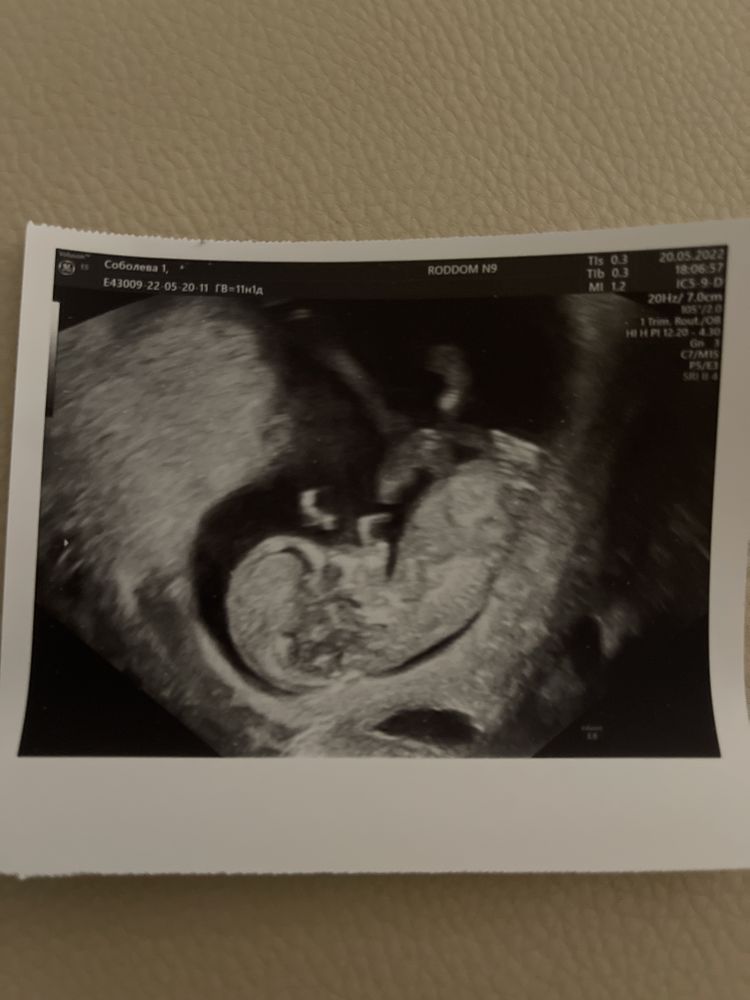

и сегодня де на сроке 11+1 мне сделали узи скрининг в жк!

предположительно узист сказала что риски минимальны, но мол ждём кровь. Так же она ругалась что меня записали на 11 неделе, а не после 12 типа ей ничего не видно..

А вот на платный скрининг мы идём 27 числа, вместе с мужем, к тому моменту будет готова кровь которую сдавали платно и срок будет 12 недель . Так что рассчитываем узнать пол и хочу чтоб муж посмотрел и послушал сердечко 💓 В общем жду 27) первое фото прилагаю